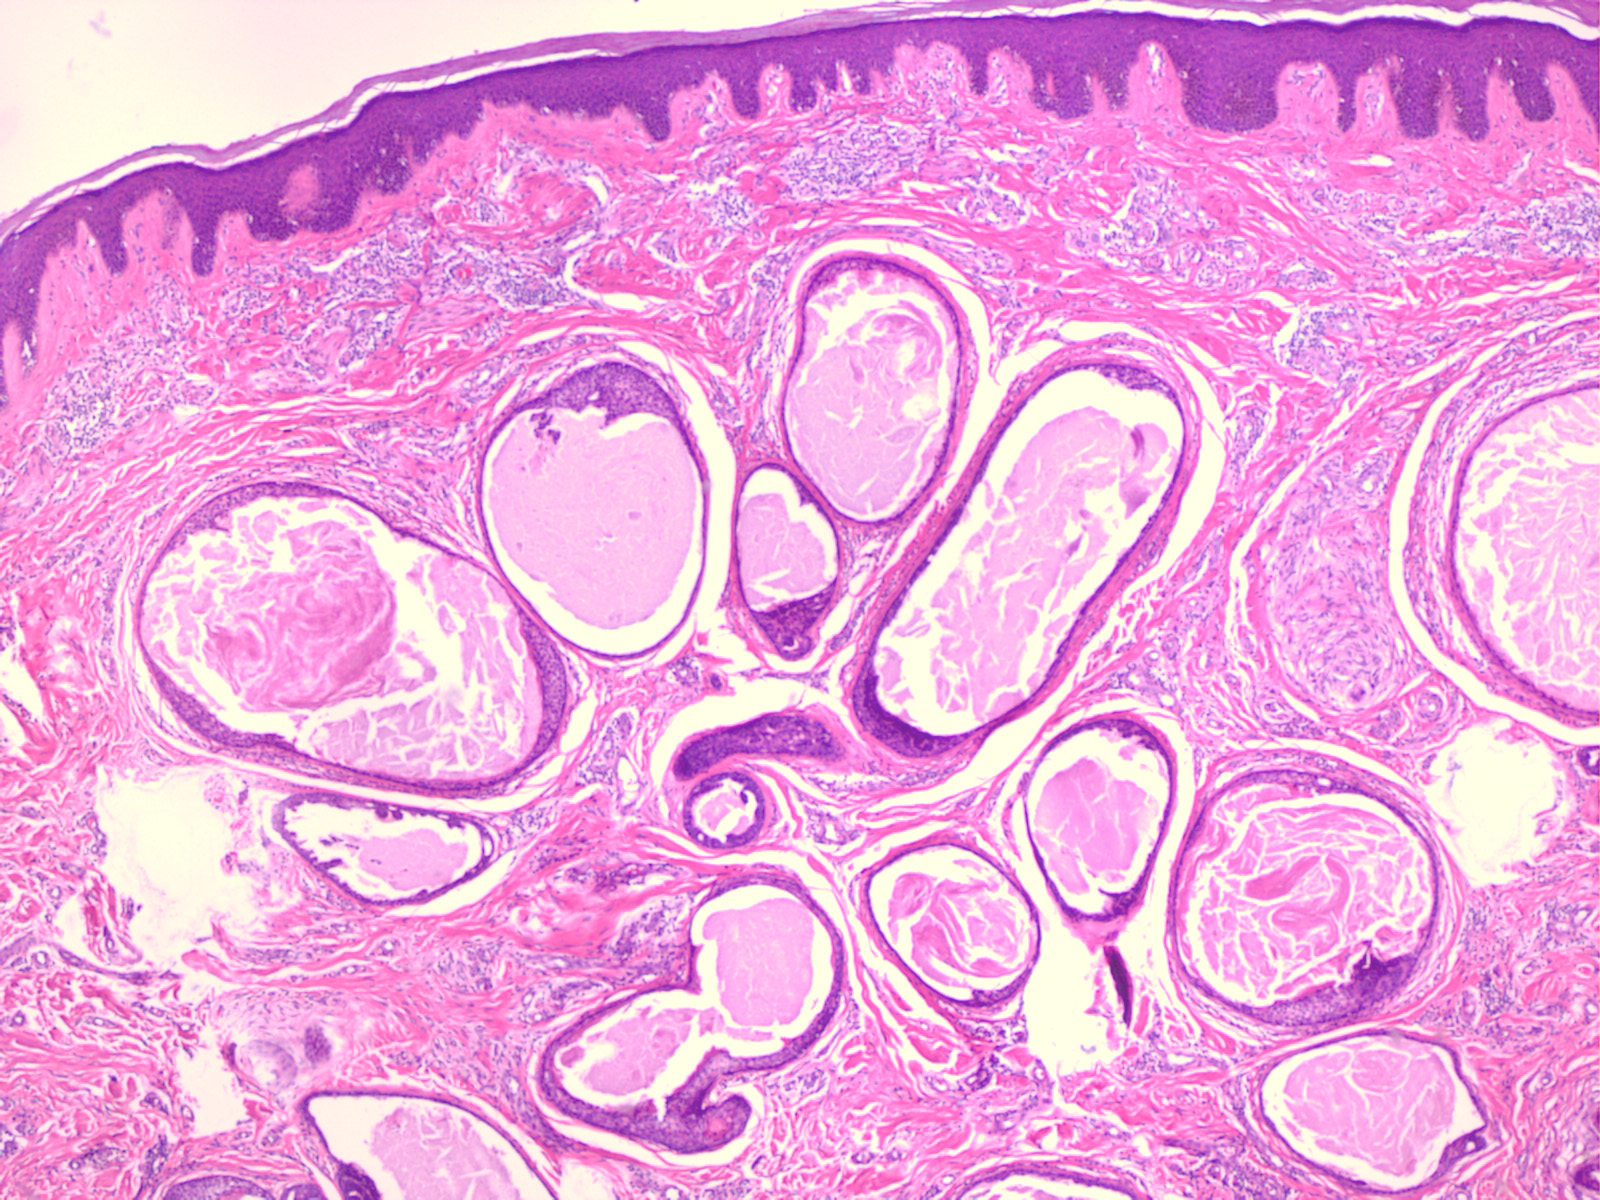

Papillary eccrine adenoma = الغدوم الناتح الحطاطي